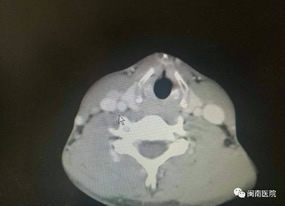

患者CT检查情况 患者CT检查情况 颈部手术切口设计

小庄是在1个月前无意中发现颈部肿大的,在外地某市级医院做了彩超检查,诊断为“双侧甲状腺结节”。随后在当地另一家部队医院做了细针穿刺,病理考虑为良性病变,为 进一步确诊,他慕名来到“医联体”找到综合外科一病区主任兼普外科主任张惠灏为其进行了详细的检查。经查,初步诊断其为右侧甲状腺癌并右侧颈部淋巴结转移,需马上安排 住院检查。随后,经颈部CT增强检查证实了专家的判断,而且还发现了原发灶侵及部分气管,颈部淋巴结转移也比较厉害。鉴于患者年轻,为保证手术的彻底性,专家决定采用改 良术式为患者行全甲状腺切除和右侧功能性颈部淋巴结清扫术。